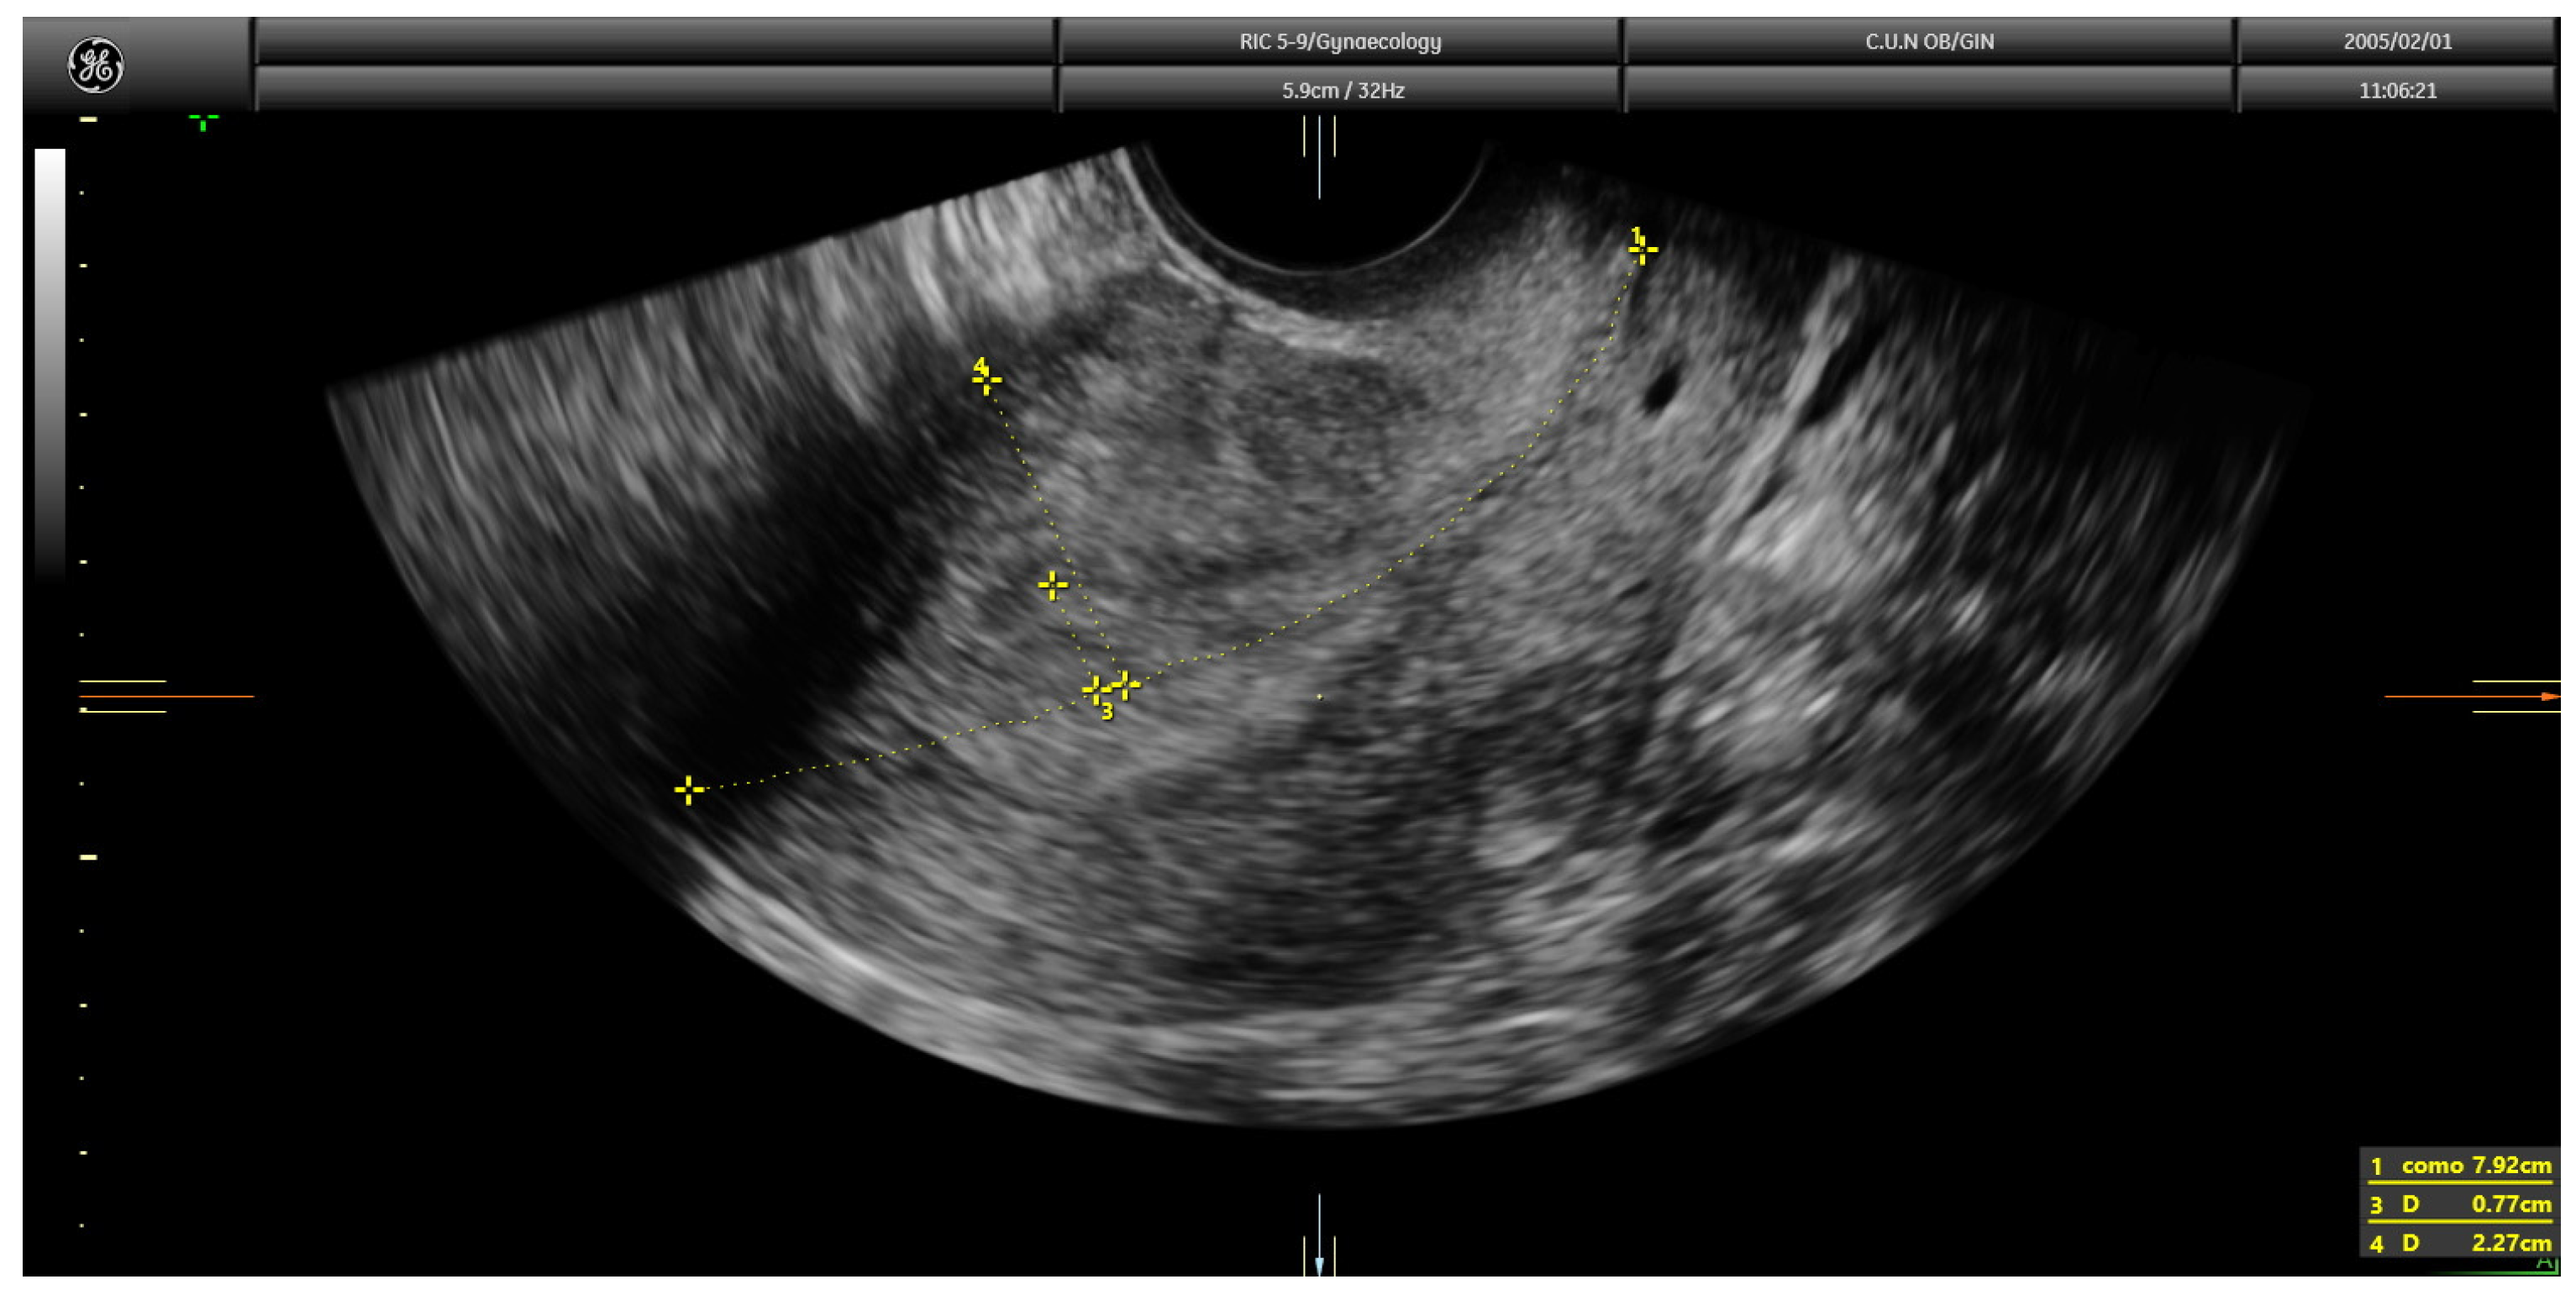

Current guidelines recommend the assessment of myometrial infiltration by magnetic resonance imaging or transvaginal ultrasound in the pre-operative work-up of women with endometrial cancer [4]. Both techniques offer similar diagnostic performance [5]. However, expertise is clearly needed when ultrasound is used [4]. Myometrial infiltration assessment by transvaginal ultrasound can be conducted using several approaches, namely examiner’s subjective impression, Karlsson’s method and Gordon’s method [6]. When using the examiner’s subjective impression, the depth of myometrial infiltration is estimated by assessing the point at which the myometrium–endometrium interface is not identified clearly and then by assessing the supposedly tumor-free myometrial wall at this point. The opposite myometrial wall is used for comparison, and, if marked asymmetry is found, deep (≥50%) infiltration is assigned; if myometrial thickness was similar in both myometrial walls, superficial (<50%) infiltration is assigned. In the Gordon’s approach, the ratio of the distance between the maximum tumor depth and total myometrial thickness is estimated. If the ratio is <50%, myometrial invasion is estimated as less than half of the myometrium; in contrast, if the ratio is >50%, it is classified as more than half of the myometrium (Figure 1).

After this, each trainee had to visualize 45 videoclips of TVS assessment of the uterus from cases of endometrial cancer already treated surgically. The number of 45 videoclips was set arbitrarily. All real-time examinations and videoclip recordings had been performed by the trainer. Doppler assessment was not included in the videoclip. Videoclips were randomly selected by the trainer from the Department imaging database. The ratio of cases with <50% and ≥50% of myometrial infiltration was 4:1. The machine settings that were used were standard ones; they included the use of harmonics with a frequency of 3–7 MHz and medium gain. Videoclip duration was about 1–2 min. The time allowed to the trainee for visualizing each videoclip was up to five minutes. Definitive histology after uterus surgical removal was used as a reference standard. All trainees had to state whether myometrial infiltration was ≥50% or <50% (Figure 3 and Figure 4).

Figure 4. Transvaginal ultrasound showing a case of deep infiltration in endometrial cancer according to subjective impression.